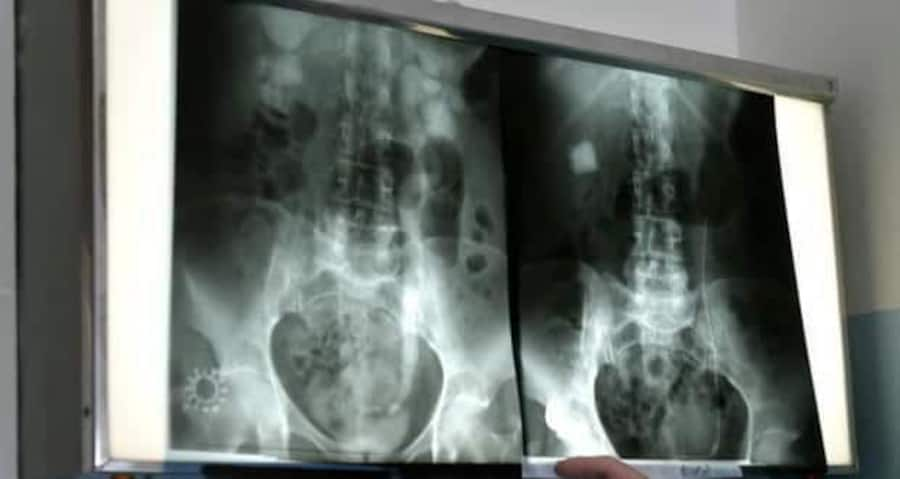

Kidney-xrayKidney stones afflict millions of people worldwide every year, triggering a crippling pain that is among the worst known to man.

Most kidney stones form when the urine becomes too concentrated, allowing minerals like calcium to crystallize and stick together. Diet plays a role in the condition -- not drinking enough water or eating too much salt (which binds to calcium) also increases the risk of stones.